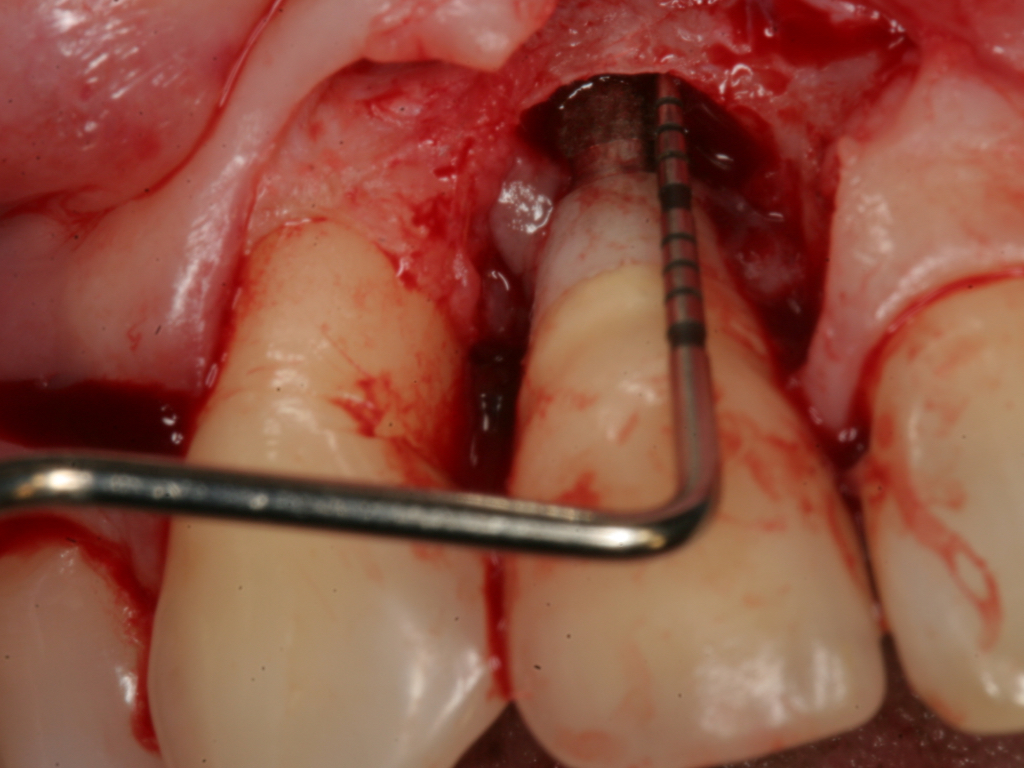

Fig 7. Probing of the buccal surface reveals additional loss of attachment around the dental implant.

Figure 7

Fig 8. Flap elevation confirms circumferential bone loss.

Figure 8

Probing is useful to determine the presence of biological complications at the buccal and lingual sites of implants, which cannot be evaluated on a radiograph (Figure 6 through Figure 8). Because of the absence of a periodontal ligament, bone loss on the buccal and lingual aspects of an implant indicates loss of support for the implant and may be a sign of additional circumferential bone loss around the implant.35